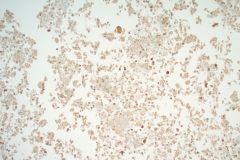

Aspirates of MTC are moderately cellular, showing a single cell pattern with occasional clustering and small aggregates. Cytologically, tumor cells can appear plasmacytoid, polygonal, or with spindle cells. Cells are uniform in size, but rare large pleomorphic cells may be present. The chromatin shows a coarse, granular, neuroendocrine pattern with inconspicuous nucleoli. Intranuclear inclusions may be seen, and nuclear grooves are rare. The cytoplasm is granular, and the amount is variable and rarely scant. Cytoplasmic dendritic processes may also be seen. Amyloid may be present in the background, although it can be identical to colloid in Papanicolaou-stained specimens. Variants of MTC include a follicular variant, papillary variant, small cell variant, giant cell variant, and a clear cell variant7. Cell blocks of MTC typically stain positive for calcitonin, CEA, TTF1, synaptophysin, and chromogranin, and are negative for thyroglobulin and PAX-88,9.

The tumor cells of this case presentation posed a diagnostic challenge due to their divergence from the typical cytological appearance of MTC. The majority of tumor cells had scant cytoplasm, including cells that resembled naked nuclei and cells with a plasmacytoid appearance. A diagnosis of MTC was rendered in conjunction with the patient’s elevated calcitonin level, history of MTC and MEN2, and comparison to the patient’s previous two MTC diagnoses.